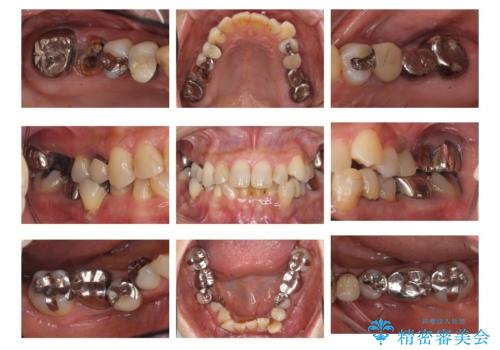

- 転倒して前歯を強打してかけてしまった、ぐらつくとのことで来院。

応急でみてもらった歯科医院で隣の歯と接着剤で留めてもらったとのこと。

歯の神経の状態を見たところ、前歯3本とも神経が死んでしまっていました。

また、左上犬歯の詰め物は途中で脱離し、セラミックでの修復をご希望されたため、一緒に治療しました。